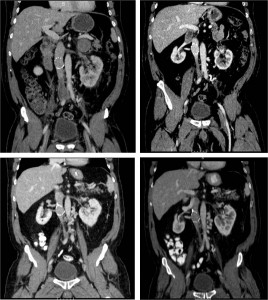

The mechanism of post-phlebitic symptoms is not fully understood. On the one hand it is probably related to venous destruction and especially valve destruction. This is why prompt catheter directed thrombolysis makes sense (see below) and graded compression stockings work (see below). An example of progressive venous atrophy after thrombosis of a retained inferior vena cava filter may be seen in the image below. The patient experienced progressive symptoms of heaviness of his lower extremities, consistent with post-phlebitic syndrome. This is, of course, an out of the ordinary case: